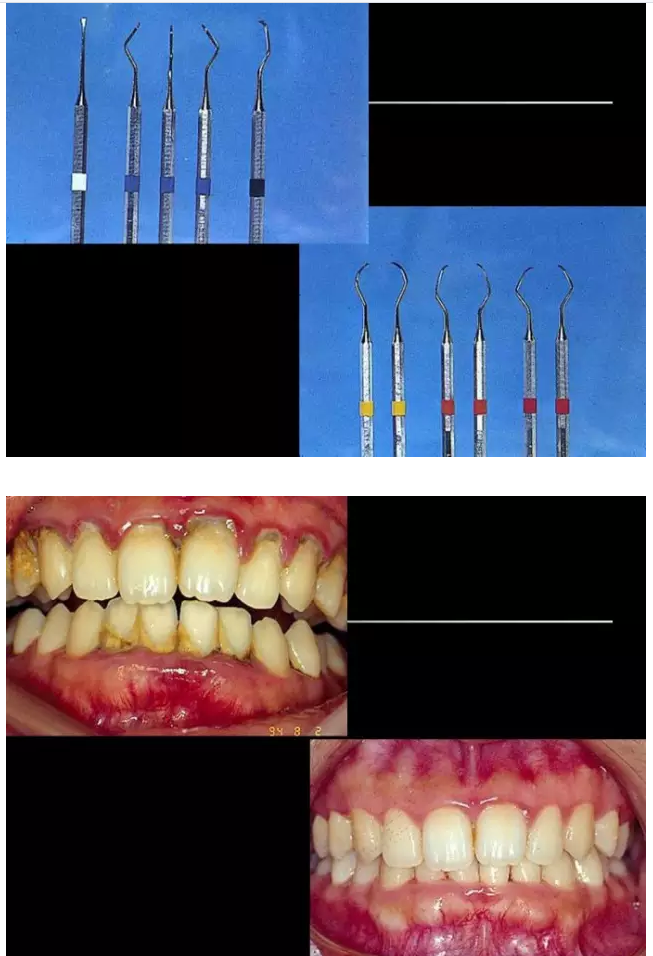

相關(guān)牙周防治